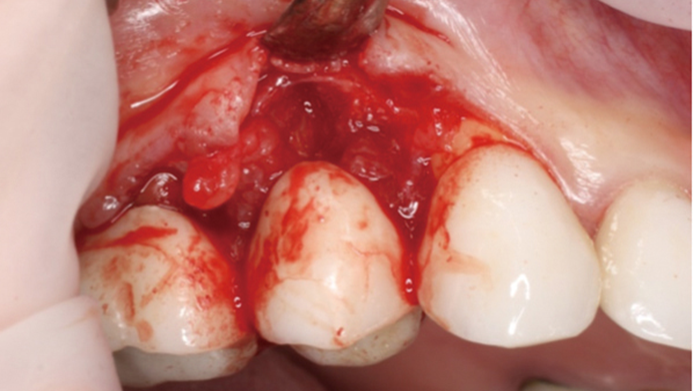

Clinical case: Extraction, immediate implant placement, & provisionalization

- Courtesy of Dr. Iulian Filipov, Romania -

Keywords

AnyRidge, R2GATE, guided surgery, immediate placement, immediate provisionalization, initial stability, Dr. Iulian Filipov, #25, maxillary posterior, immediate loading, Mega ISQ